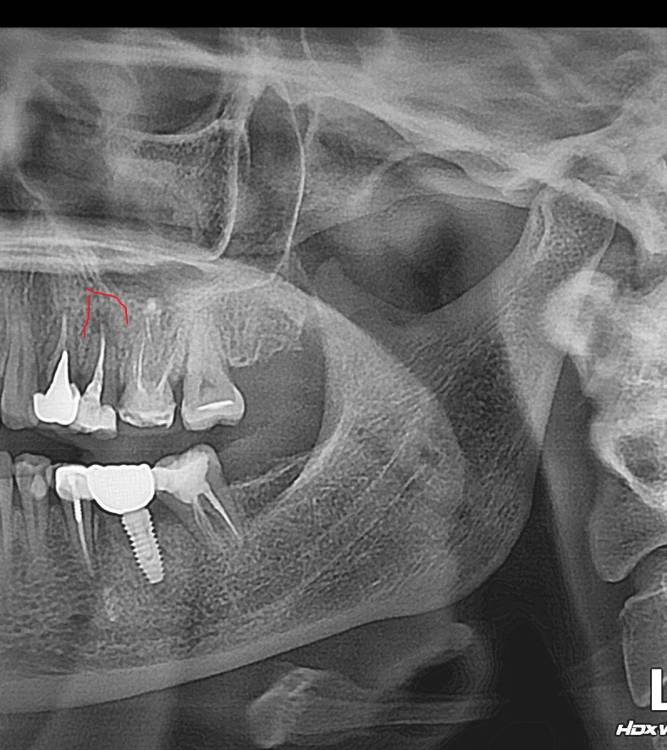

руслана Опубликовано 27 февраля, 2024 Поделиться Опубликовано 27 февраля, 2024 Здравствуйте.Как считаете можно это вылечить .5 верхний Ссылка на комментарий

руслана Опубликовано 27 февраля, 2024 Автор Поделиться Опубликовано 27 февраля, 2024 Спасибо за ответ. Коронковая часть зуба целая. КТ ,к сожалению, нет возможности приложить. Зуб был пролечен 3года назад. вот выросло.. Ссылка на комментарий

Carioznik Опубликовано 27 февраля, 2024 Поделиться Опубликовано 27 февраля, 2024 Предположительно: успешный прогноз сомнительный. Нужно смотреть очно +кт Ссылка на комментарий

руслана Опубликовано 27 февраля, 2024 Автор Поделиться Опубликовано 27 февраля, 2024 49 минут назад, Carioznik сказал: Предположительно: успешный прогноз сомнительный. Нужно смотреть очно +кт Почему? Большой размер? Мнения врачей разделились очно. Хирург сказал удалять и имплант, стоматолог сказала, что это не совсем киста пробуем спасать. Ссылка на комментарий

Carioznik Опубликовано 27 февраля, 2024 Поделиться Опубликовано 27 февраля, 2024 (изменено) 55 минут назад, руслана сказал: Большой размер? Размер не имеет значения. И это не киста. У меня вопросы к верхушке корня, судя по этому снимку- она "разъедна" (наружная воспалительная резорбция) , а значит возможно полноценно обработать и запломбировать канал не удастся. Также сильно расширена верхняя часть канала и если снять пломбу -то от зуба останется не много, вопрос что там с прикусом... и соотношении этого зуба со встречными зубами -это тоже всё может отразиться на сроке службы зуба. У перелечивания процент неудачи равен около 20. А если учитывать ,те моменты, которые я вижу на этом снимке -и того больше. Нужна хорошая диагностика , чтобы принять оптимальное решение по этому зубу. Сделать можно всё, вопрос сколько это простоит в долгосрочной перспективе. И на этот зуб нужна коронка. Итого, что пока я вижу: перелечивание (без гарантий)+ коронка =неизвестный результат, с ценой приближающейся к импланту. Поэтому , повторюсь, нужна хорошая диагностика, которую в интернете, заочно, Вы никогда не получите Изменено 27 февраля, 2024 пользователем Carioznik Ссылка на комментарий